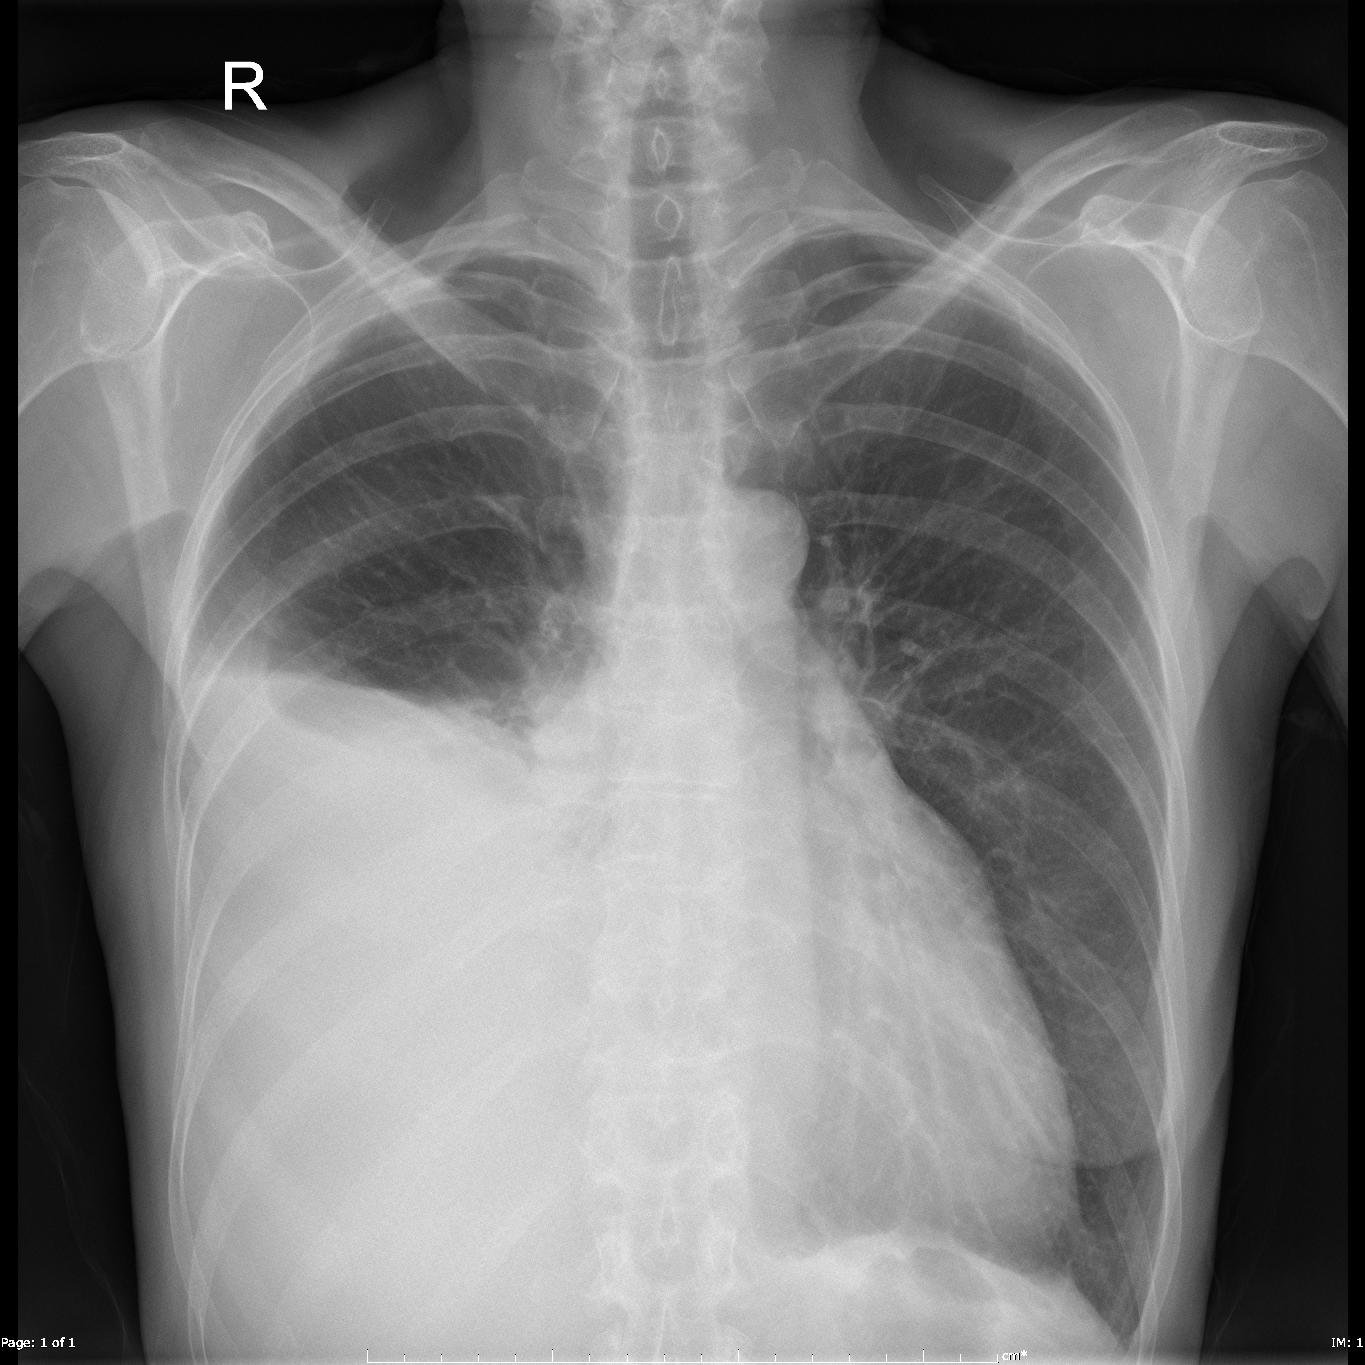

Do ponto de vista clínico, os sintomas mais comuns são a falta de ar, tosse e dor torácica. A etiologia do derrame pleural determina outros sinais e sintomas. O método inicial mais comum para confirmar a existência de derrame pleural é a radiografia do tórax póstero-anterior e lateral, verificando-se no derrame livre o apagamento do seio costodiafragmático, se volume >175ml. A TAC está indicada na avaliação do parênquima pulmonar e mediastino, distinção entre empiema e abcesso, suspeita de tromboembolia pulmonar e estudo de loculação, espessamento e nodularidade pleural. A ecografia torácica é o exame de eleição perante a suspeita de derrame pleural, com elevada sensibilidade diagnóstica, permitindo avaliar o volume do derrame, as características do espaço e líquido pleural e a melhor localização para punção, diminuindo as complicações das técnicas invasivas.